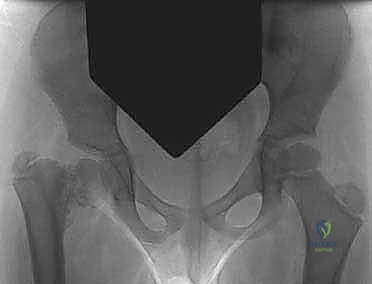

تُعد الأشعة السينية (X-rays) للحوض (الأمامي الخلفي AP view) الأداة الأهم والأكثر حسماً في تشخيص الفحج الرضخي النمائي. من خلال هذه الأشعة، يقوم الدكتور هطيف بـ:

1. قياس زاوية عنق الفخذ (NSA) لتأكيد هبوطها تحت 110 درجات.

2. قياس زاوية هيلجنراينر (HEA) لتحديد خطة العلاج (هل تحتاج جراحة فورية أم مراقبة).

3. البحث عن العلامة المميزة: الشظية العظمية المثلثية (Triangular fragment) في الجزء السفلي من عنق الفخذ، والتي تعطي صفيحة النمو شكل حرف Y المقلوب.